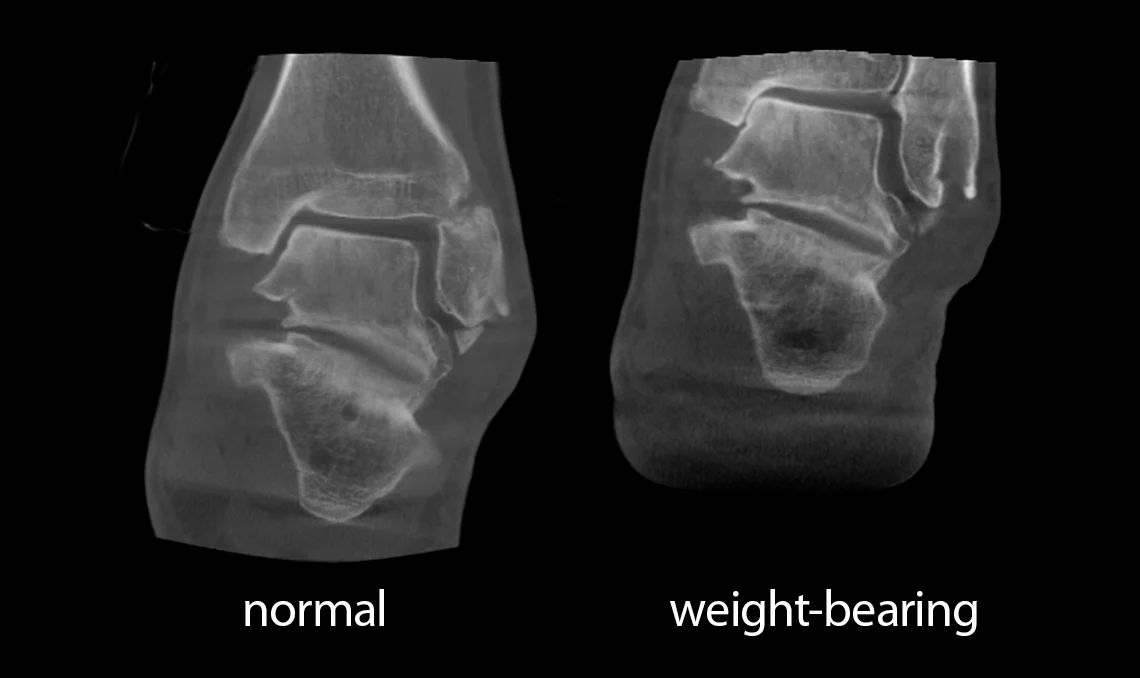

Avantages de l’imagerie 3D en charge

Intégrée aux évaluations préopératoires, cette imagerie améliore la prise de décision chirurgicale, réduit le risque de complications et contribue à de meilleurs résultats thérapeutiques. Elle dépasse les limites des techniques conventionnelles liées aux effets de projection et au chevauchement des structures, en offrant une représentation anatomique plus fidèle dans une position naturelle et fonctionnelle. Cette technologie apporte également une meilleure analyse du pincement des espaces articulaires et d’autres atteintes qui peuvent passer inaperçues avec les méthodes d’imagerie traditionnelles.